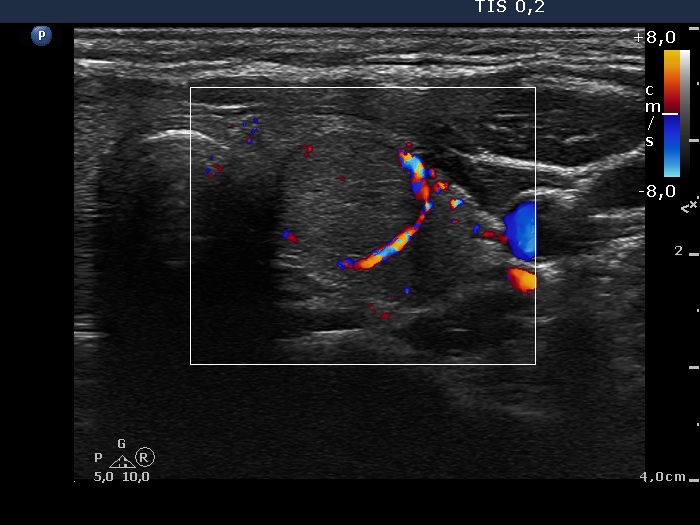

Discrete lesion or nodule in Hashimoto's thyroiditis - case 10 (95)

Follow-up investigation 3 months after the first visit (ultrasonographic picture 6)

Left lobe, transverse scan, color Doppler mode.